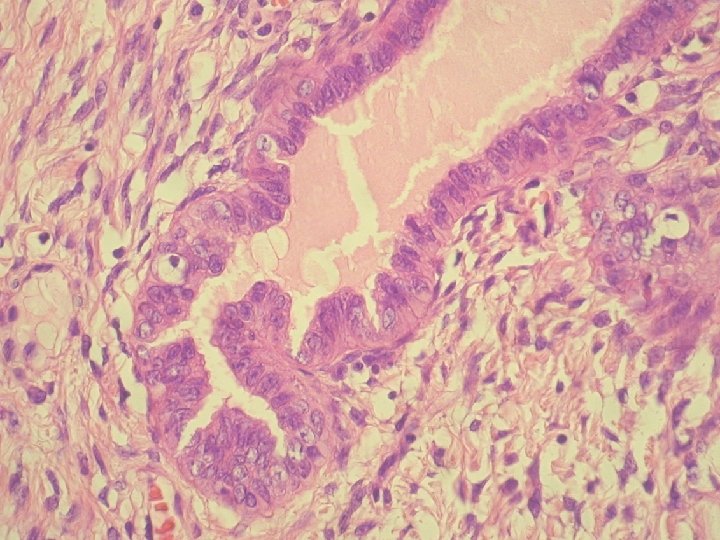

prolaps tuby asociovaný s exuberantnou angiomyofibroblastickou strómou

Klinicky: chronická abdominálna bolesť, dyspareunia polypoidné hemoragické masy Ø Histologicky: prezencia tubálneho epitelu s

Klinicky: chronická abdominálna bolesť, dyspareunia polypoidné hemoragické masy Ø Histologicky: prezencia tubálneho epitelu s variabilnou architektonikou v edematóznej, prevažne fibrotickej stróme Ø glandulárne prevažne tubálne inklúzie z malých epiteloidných buniek s eozinofilnou cytoplazmou, s riasinkami, sekretorické a „peg“ cells

Ø hladkosvalové vlákna a lymfoplazmocytárny infiltrát Ø bohatá vaskularizácia v retiformnej stróme, miestami aj

Ø hladkosvalové vlákna a lymfoplazmocytárny infiltrát Ø bohatá vaskularizácia v retiformnej stróme, miestami aj myxoidnej Ø Imuno: silná desmin pozit. Ø CD 34, S-100, alfa aktin, CK, calponin negat. Ø prezentovaná reaktívna stromálna proliferácia publikovaná v dvoch „case reportoch“